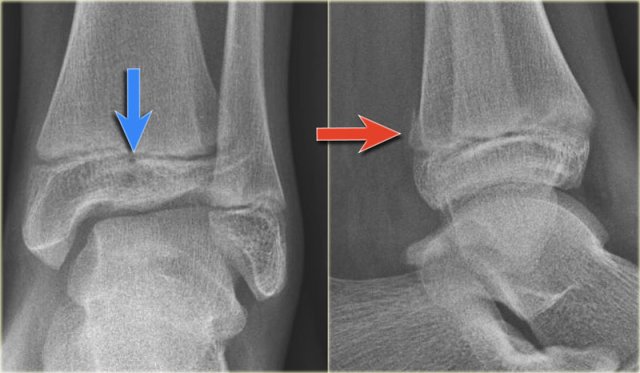

Study the images and then scroll to the next images.

The fracture through the epiphysis can be easily missed (blue arrow).

The fracture through the growth plate is only seen on CT.

Continue with the CT images.